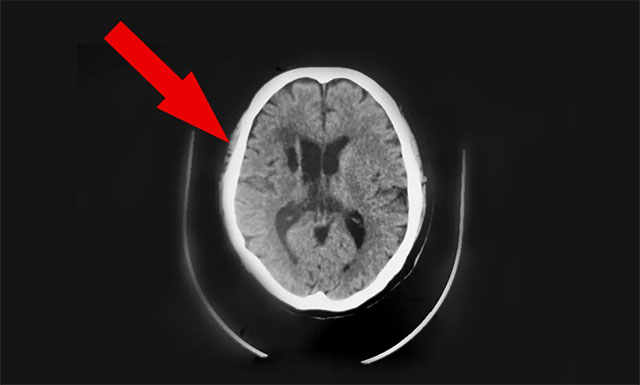

近期,因頭暈不適感持續(xù),前往上海某醫(yī)院就診檢查。行頭顱CT發(fā)現(xiàn):1. 兩側(cè)半卵圓中心區(qū)及基底節(jié)區(qū)多發(fā)腔隙性腦梗塞;2. 左小腦及右側(cè)基底節(jié)區(qū)斑片軟化灶;門診擬以“頸內(nèi)動(dòng)脈狹窄、腦梗死”收入。治療一個(gè)月后無明顯改善。為求進(jìn)一步治療,9月中旬胡夫人陪同患者胡某慕名轉(zhuǎn)往上海藍(lán)十字腦科醫(yī)院,由6B神經(jīng)外科潘仁龍主任接診。

在潘仁龍、吳志群及黃秀夫三位醫(yī)生會(huì)診下,基于患者近半個(gè)月主訴有頭暈,偶有行走不穩(wěn),頭暈癥狀明顯,次數(shù)較前明顯增加。9月16日CT頭顱CTA+CTP 示病患右側(cè)大腦中動(dòng)脈M1段、左側(cè)大腦后動(dòng)脈多處狹窄,右側(cè)大腦中動(dòng)脈中央、遠(yuǎn)端分支明顯稀疏、減少等;考慮心臟支架術(shù)后狀態(tài),基礎(chǔ)性疾病較多,顱內(nèi)多發(fā)血管性狹窄,行血管搭橋手術(shù)風(fēng)險(xiǎn)較高,建議行顳肌貼敷術(shù),以改善患者病情,提高患者生活質(zhì)量,建議盡早手術(shù)治療。

▲ 手術(shù)前